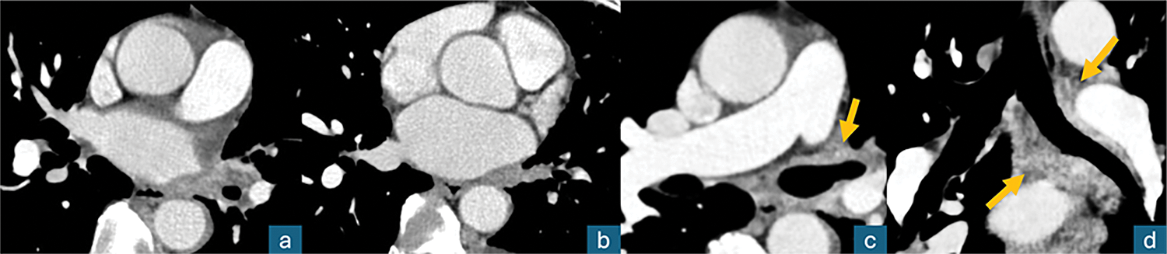

Figure 2

Contrast‑enhanced axial chest CT (mediastinal window); a, b: thrombosis of the left superior and inferior pulmonary veins; c, d: diffuse left peribronchial contrast‑enhancing infiltration (arrows), “pulmonary hilar cavernoma.”